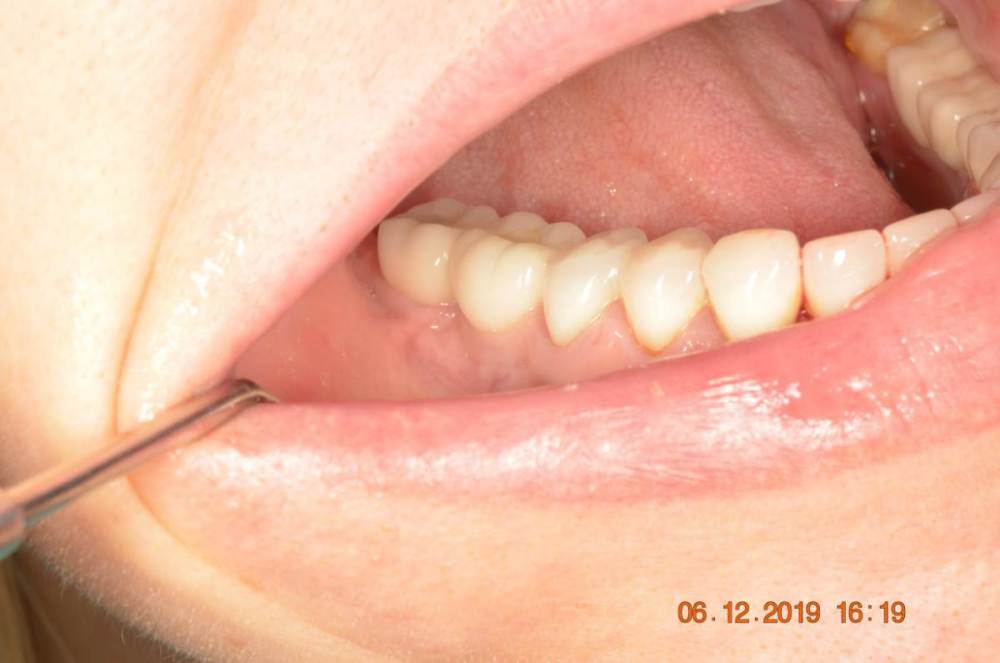

Большой Зеленый Опубликовано 7 ноября, 2022 Поделиться Опубликовано 7 ноября, 2022 Обратите внимание на даты 2 Ссылка на комментарий

Большой Зеленый Опубликовано 7 ноября, 2022 Поделиться Опубликовано 7 ноября, 2022 @Mailze Если честно ,система не совсем отечественная ,а если совсем честно то она итальянская .ВВ Дентал. Пилят винты в городе Балонья .В 2019 году я был на производстве. Потрясает конечно. Хотели перенести производство в роскосмос или в сколково ,но дальше слов не пошло. Может быть и к лучшему 1 Ссылка на комментарий